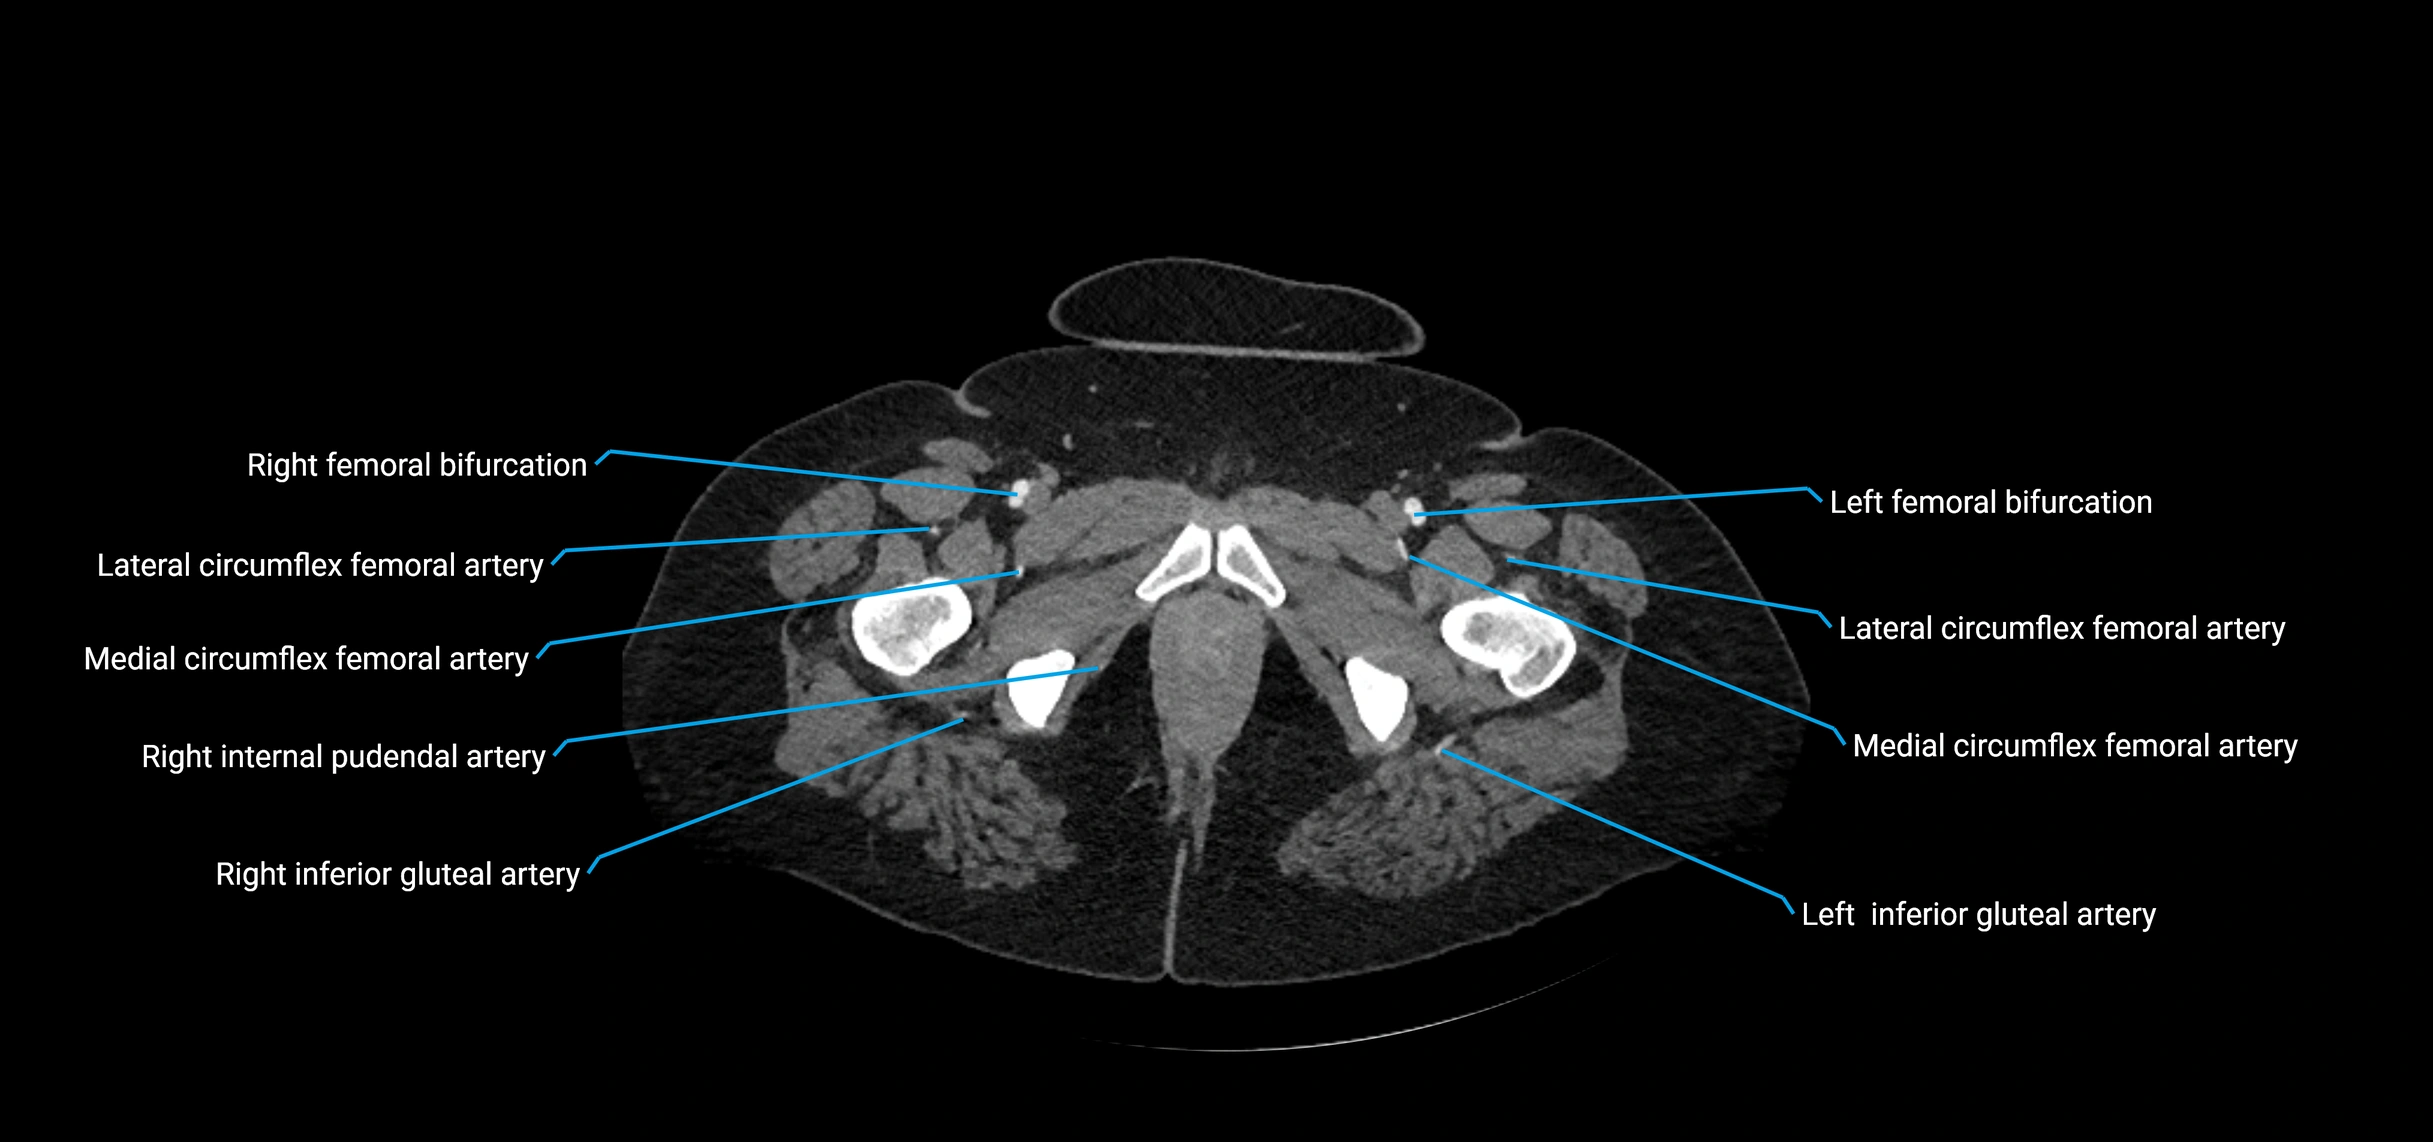

Contrast-enhanced CT (CTA):

• Gold standard for abdominal aortic imaging

• Provides excellent detail of lumen, wall, aneurysm, thrombus, and branch vessels

• Multiplanar and 3D reconstructions help in aneurysm measurement, stent graft planning, and dissection evaluation

• Detects acute rupture, traumatic injury, or occlusion with high sensitivity